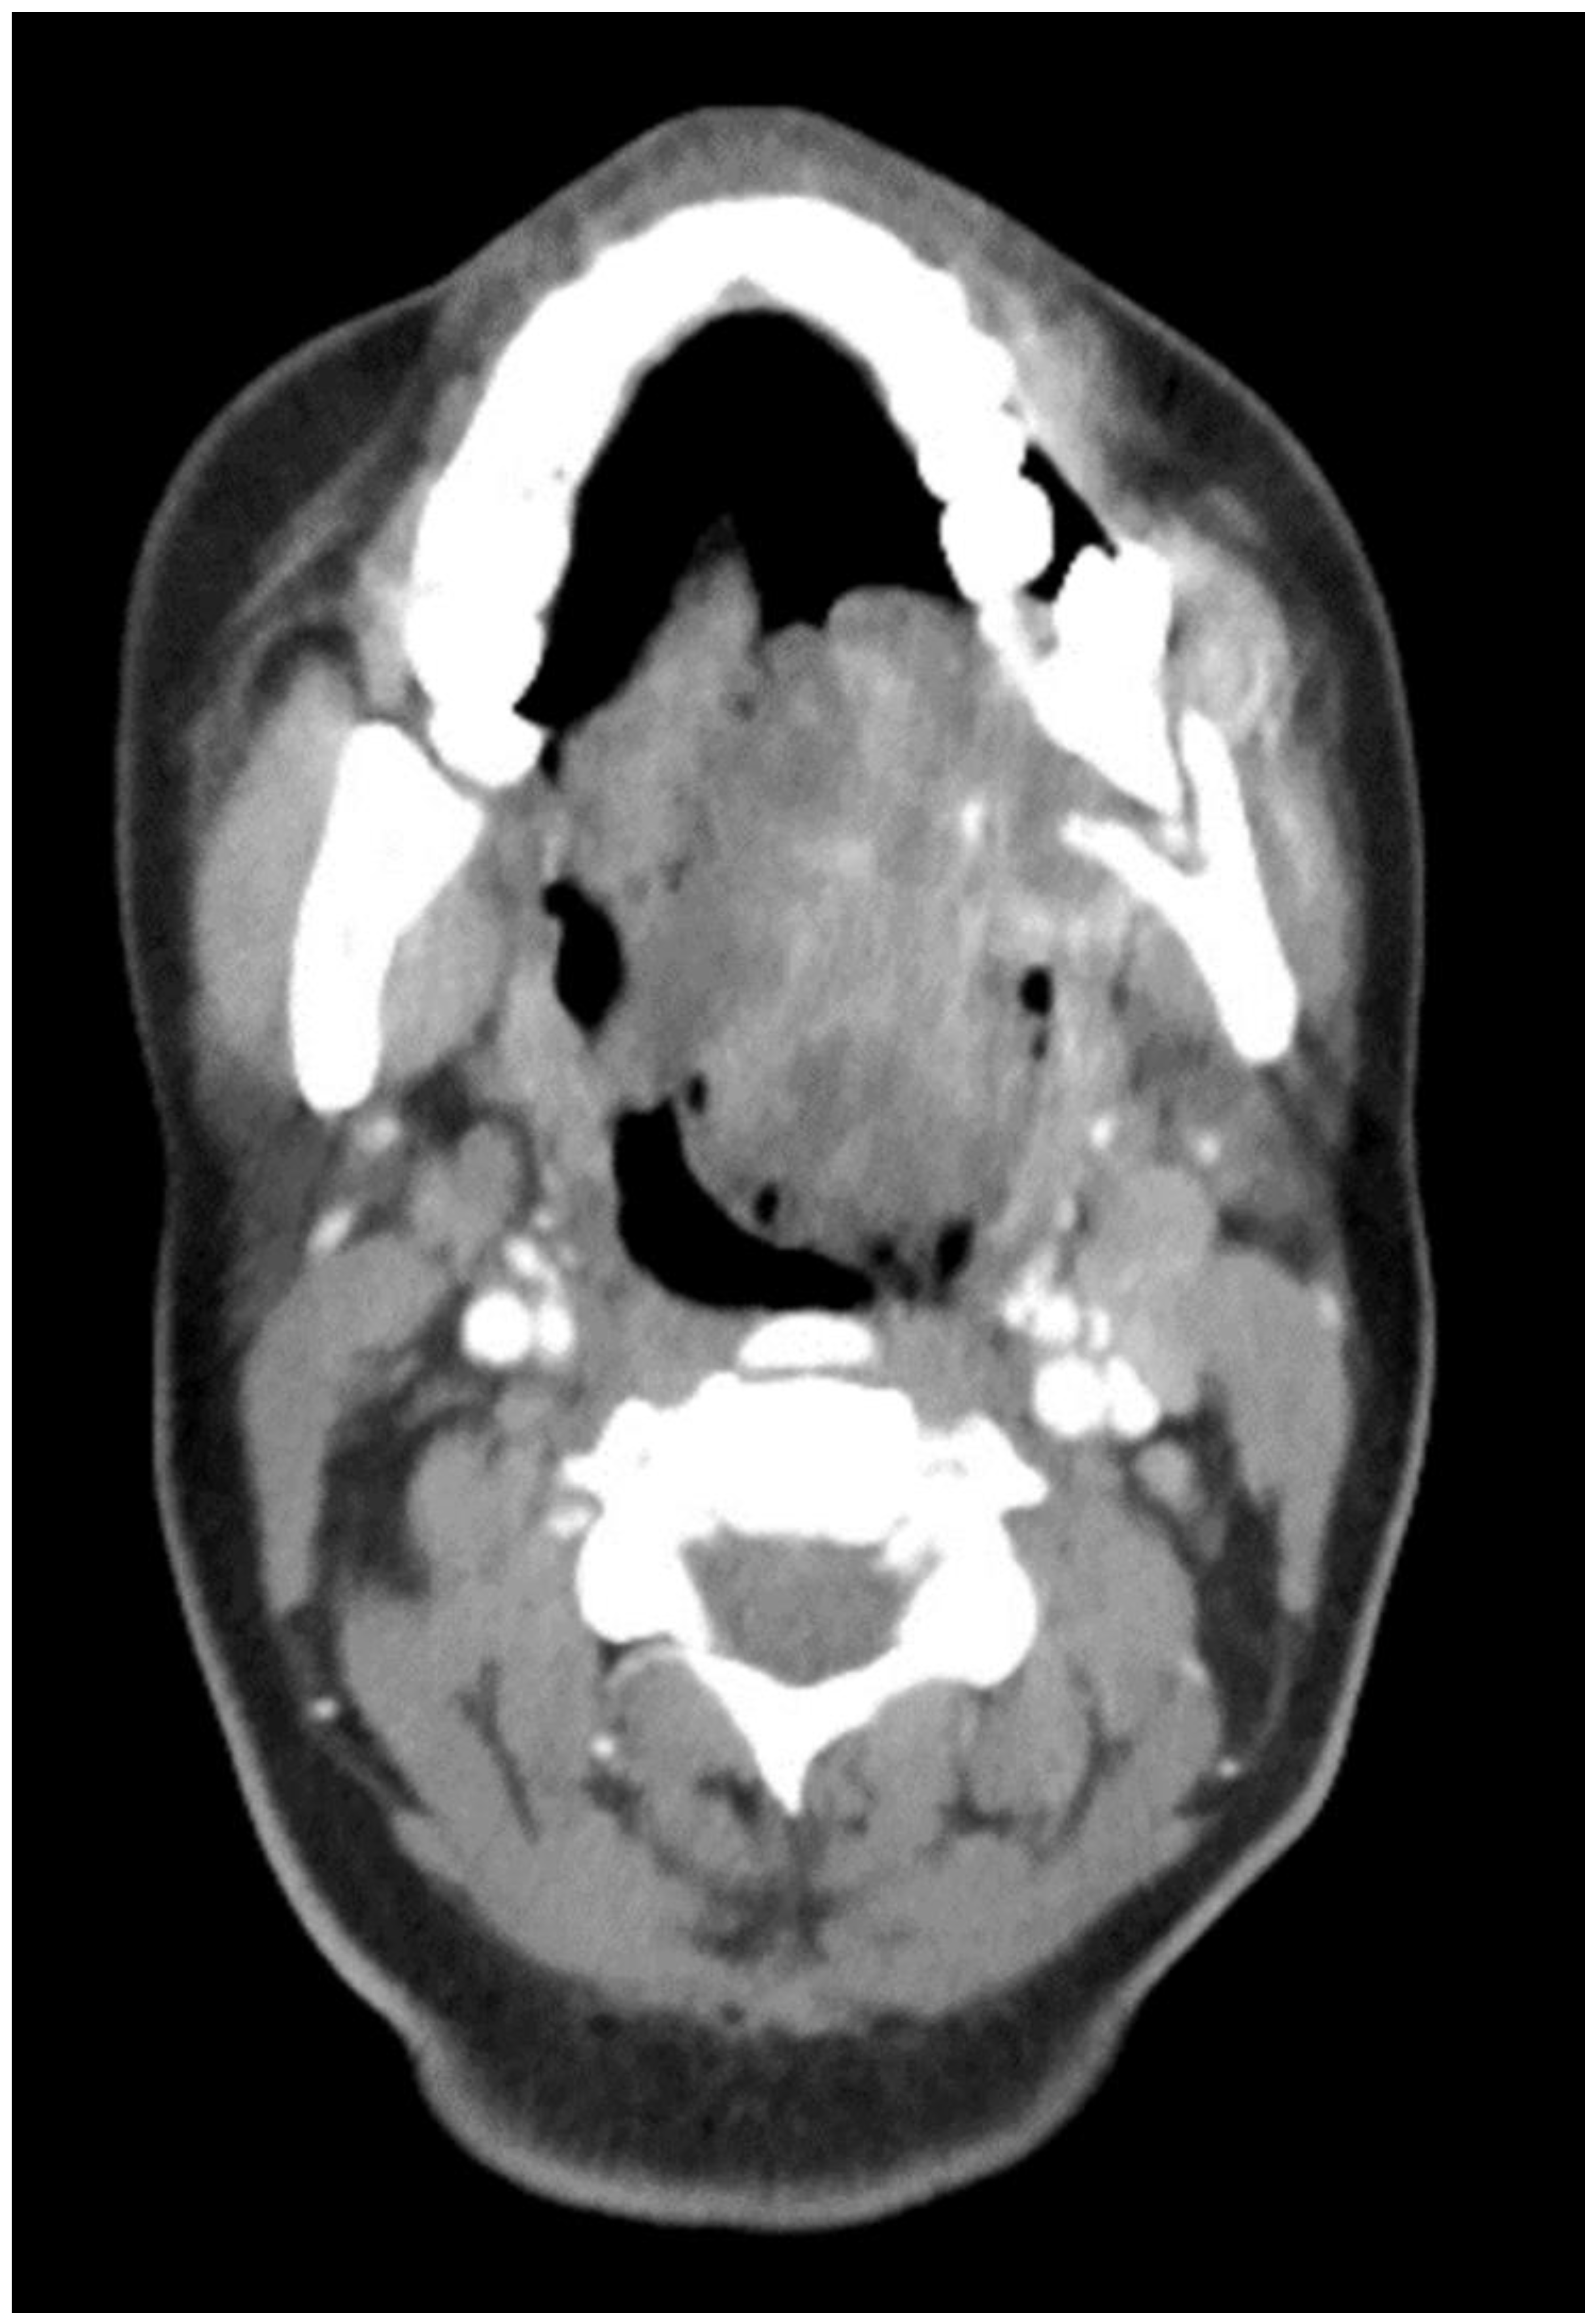

Figure 2.

CT Scan with contrast showing the mass extending to the oropharynx with complete airway obstruction.

The aim of this article is to describe the case of a 30-year-old African American female patient who presented at the Emergency Department (ED) in May 2023 at the University of Texas Medical Branch. As per the institution’s policy, IRB approval is not required for case reports, and photographic and informed consent was obtained from the patient to publish her case in a scientific journal, with progressive dyspnea, dysphagia, difficulty managed oral secretions, and decreased oral intake for the last three weeks. The family reported that she had increased swelling for the previous month, which was thought to be an odontogenic infection. The patient was seen by another ED-provider five weeks before and was discharged home with Amoxicillin-Clavulanic acid 875 mg PO every 12 h for 7 days. Oral and Maxillofacial Surgery services were consulted for urgent evaluation. Upon examination, the patient had a large expansile ulcerative mass intraorally, extending from the left posterior mandible and completely obliterating the oropharynx (Figure 1). The patient could not lay flat and was on 4 L of Oxygen via a nasal cannula. The patient denied any medical problems, taking any medications, or any allergy to any medicines. Based on the initial examination, the decision was to proceed with an awake tracheostomy to secure the airway, direct laryngoscopy, and incisional biopsy of the mass to establish the diagnosis. The procedure was performed uneventfully, and the patient had a CT Maxillofacial and Neck with an IV contrast. The scan showed a massive, expansile mass originating from the left posterior mandibular body, invading the pharynx’s posterior wall, with a complete obliteration of the oropharynx (Figure 2). Also, there was a highly suspicious enlarged lymph node at level 1B (Figure 3).